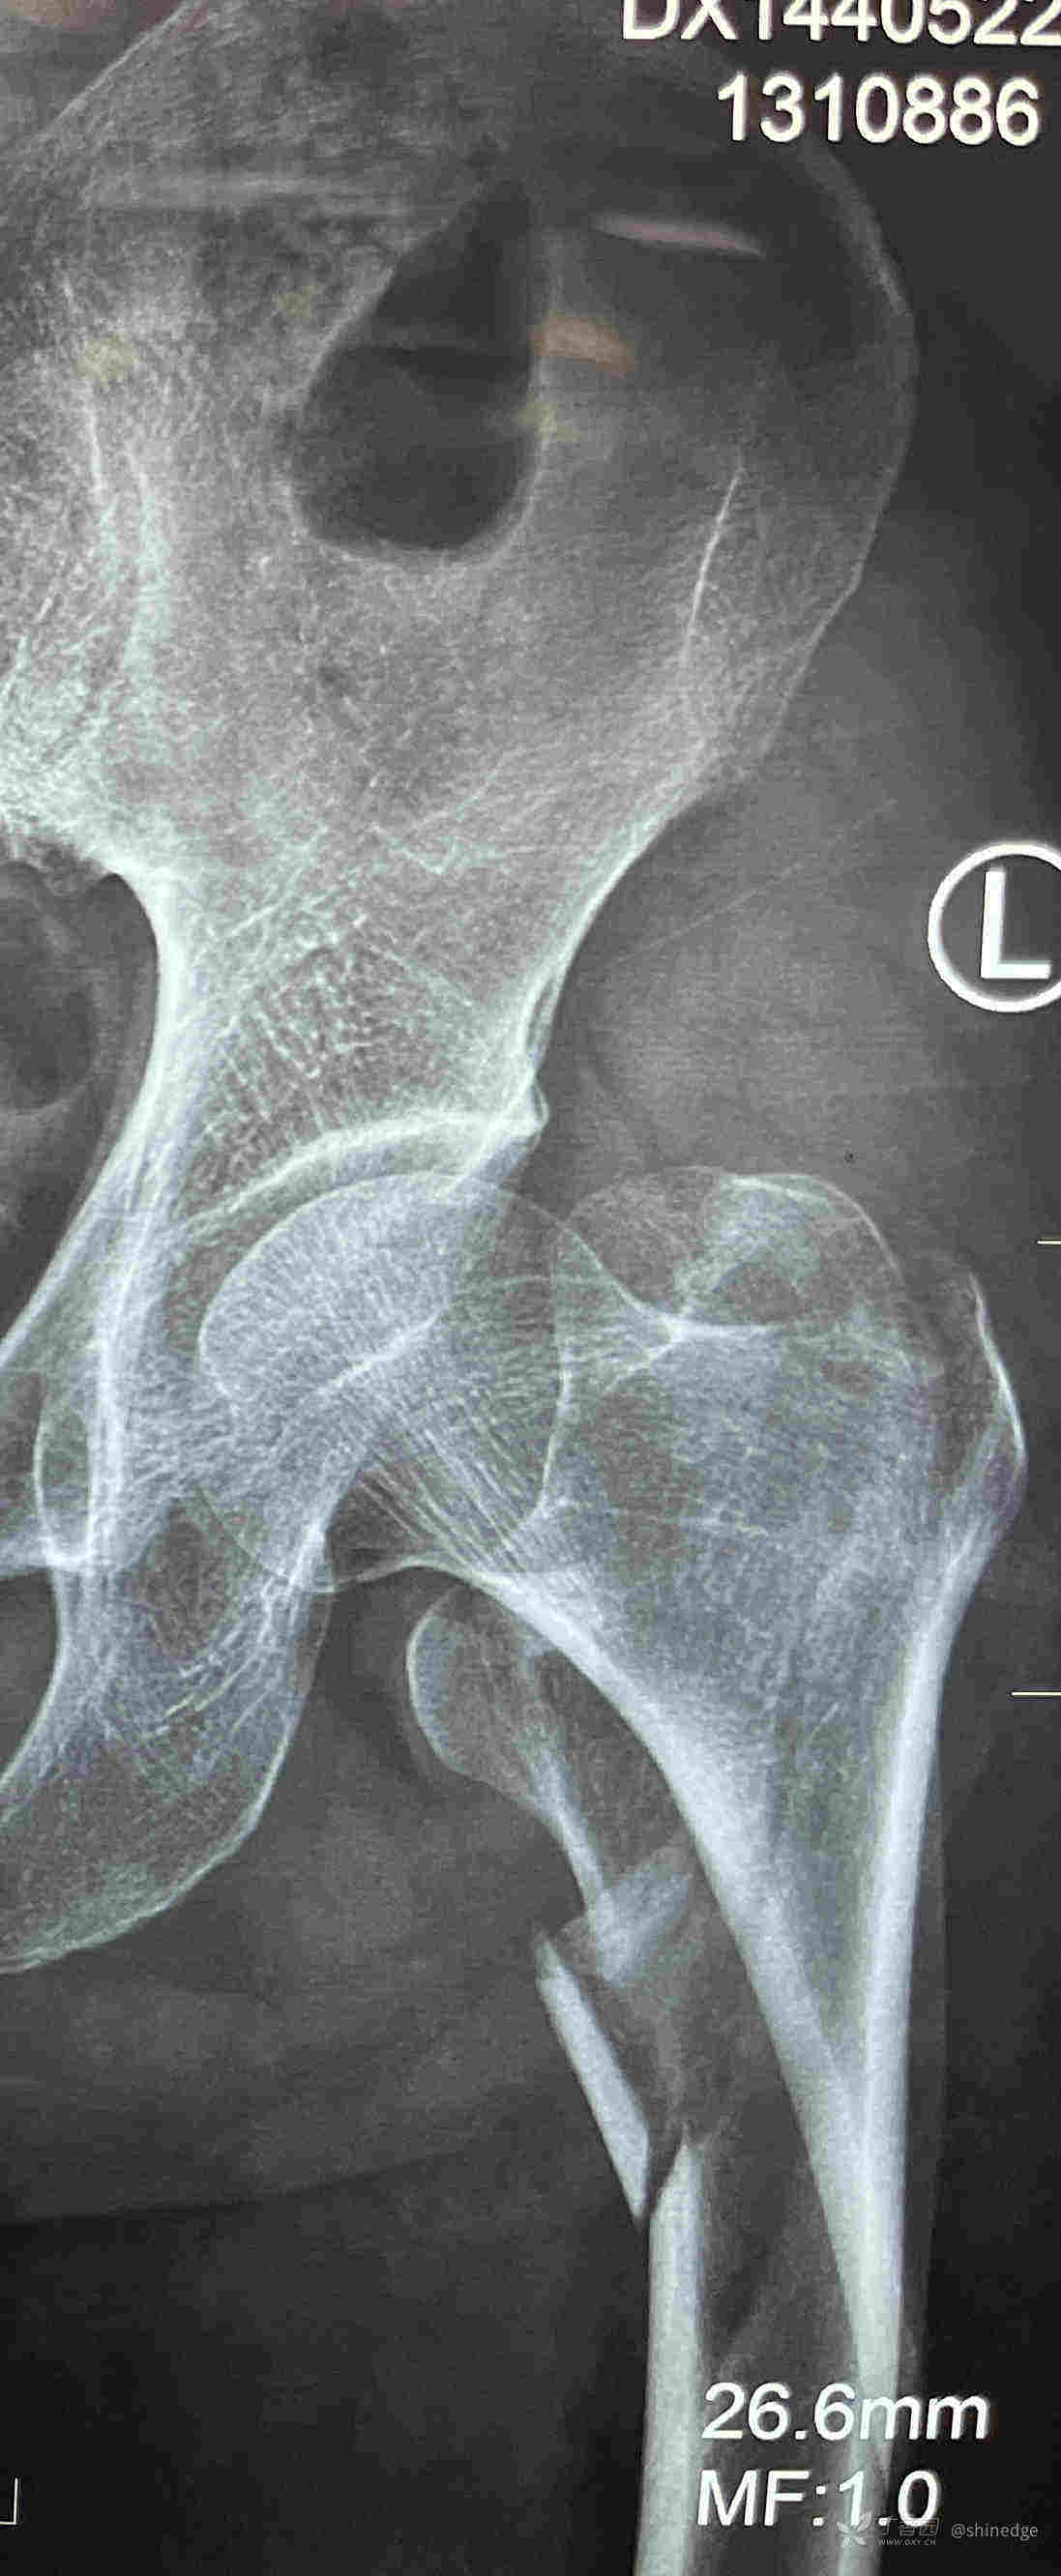

股骨近端骨折,钢丝挺好(OTA 31A2.3)

临床诊断:股骨近端骨折

讨论:上牵引床后,透视发现近端骨折块向前方移位,旁边有哥们说,不用处理,放主钉、打InterTAN头颈钉后位置会好一些,我说会好一点,但尽量做的更好一点。然后使用国产仿AO的钢丝环绕器,通过大概准备打头颈钉的切口,捆绑了一下,位置好了再置钉。